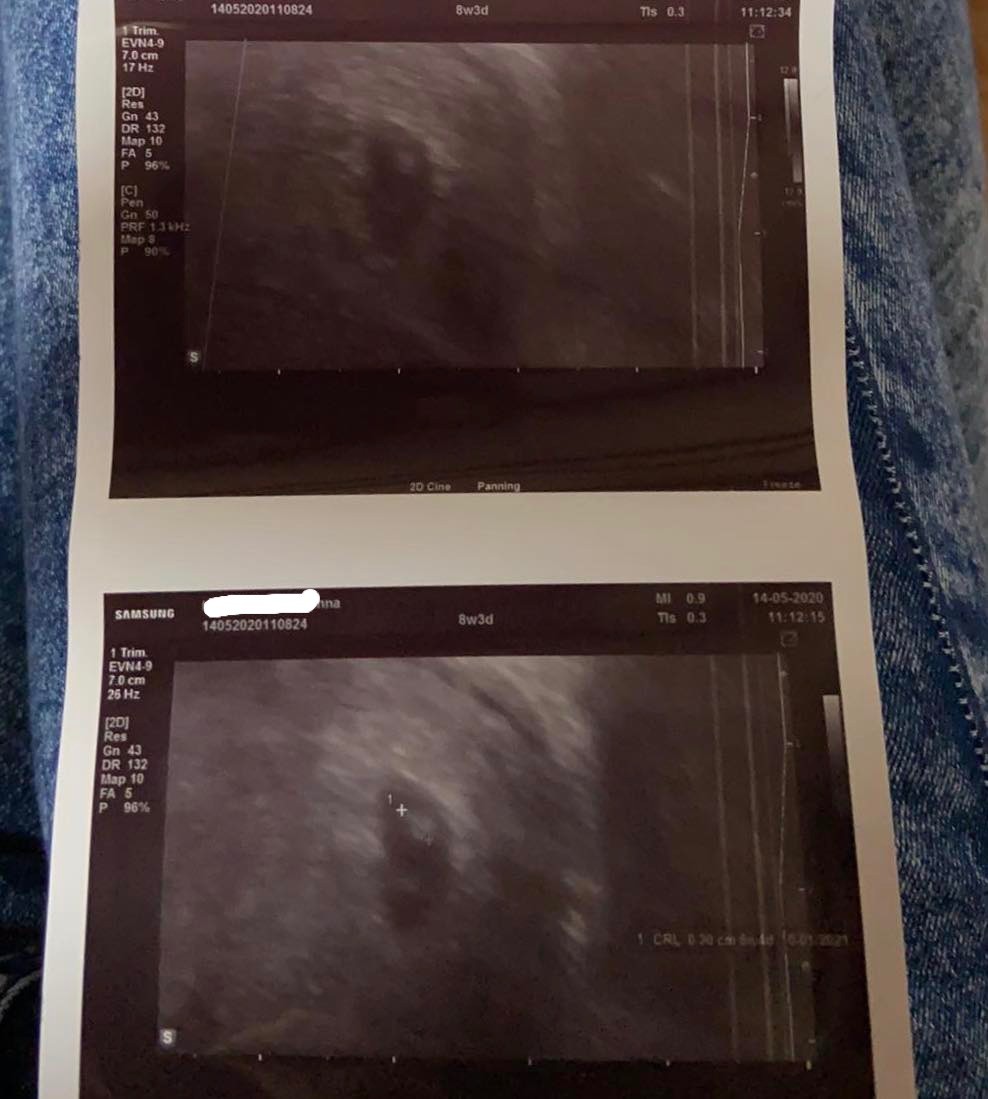

14.05 Niestety lekarz który robił mi pierwsze poszedł na zwolnienie, przyjął inny. Wykonał szybko pobieżne badanie i stwierdził ze nic z tego nie będzie bo ciąża się nie rozwija jak na ten tydzień (założył termin wynikający z miesiączki mimo ze wspominałam o opinii z poprzedniego)

Zdjęcia obu usg dodaje w załączniku. Czy faktycznie ciąża się nie rozwija i już nie ma na co liczyć? Czy któraś z was miała podobny obraz?

Na 1 zdjęciu jest jajo płodowe na drugim już zarodek crl 3cm no więc moim zdaniem się rozwija czy serduszko biło? Co masz robić co lekarz powiedział? Dlaczego jego zdaniem nic z tego nie będzie cyt. Cykle masz przecież nieregularne. Ja bym poszła jeszcze raz do lekarza z dobrym sprzetem i wypytała o wszystko

„ nic z tego nie będzie, przykro że musi przekazać taką informacje„ i że skłania się do rozwiązania... nie był zbyt wylewny w szczegóły, z miesiączki wychodził 8 tydzień a na 8 tydzień ciąża jest za mała więc nic Z tego nie będzie... poczekam jeszcze dwa tygodnie pójdę prywatnie gdzieś indziej. Chyba że coś się będzie działo (plamienia itd)...

Tak jak dziewczyny mowia poczekaj i umow sie do jakiegoś dobrego lekarza. Na 1 usg jest samo jajo na drugim juz jest zarodek. Moze faktycznie ciaza jest młodsza :)